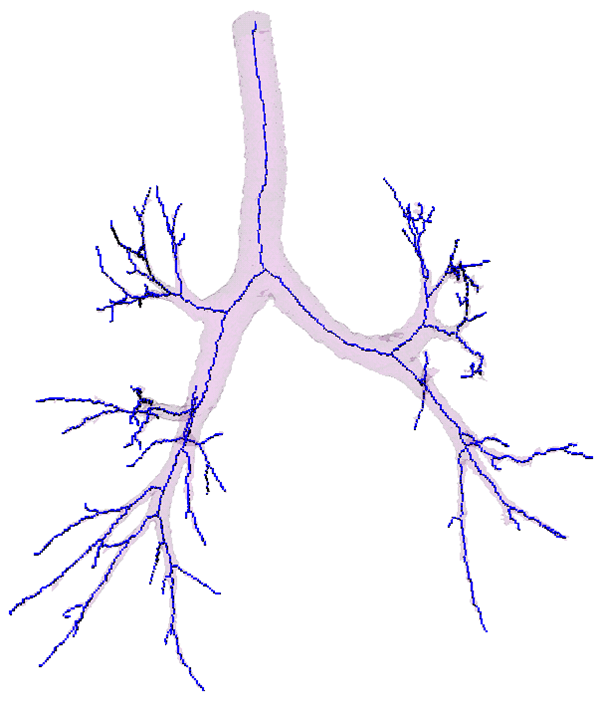

The key steps are now illustrated:

Segmentation - adaptive region growing (left), extracting centerlines - topologically and geometrically correct thinning (middle), and excluding branch-areas based on 3D distance map calculation (right).

Partitioning centerlines in a formal tree data structure (left), partitioning segmented tree via isotropic label propagation (middle), and quantitative analysis formal XML tree with associated measurements (right).